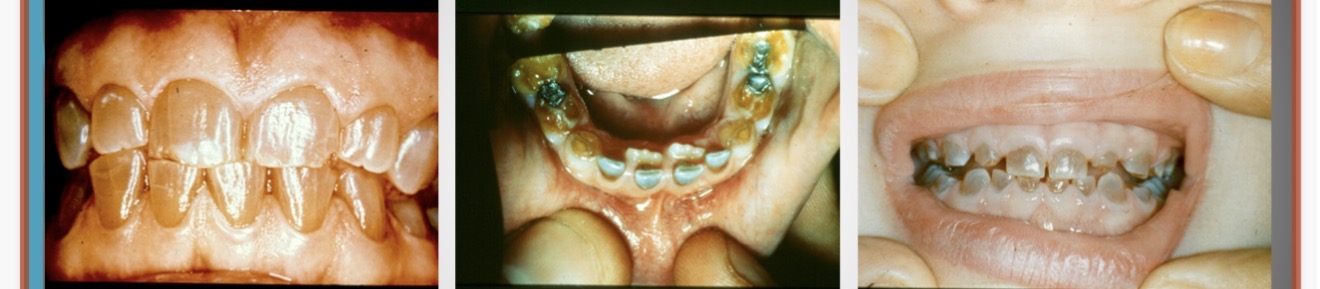

Condition?

Drug induced gingival enlargement

What drugs can cause gingival enlargement?

cyclosporine (SandimmuneĀ®)

dilitiazem (CardizemĀ®)

nifedipine (Procardia)

diphenylhydantoin (DilantinĀ®)